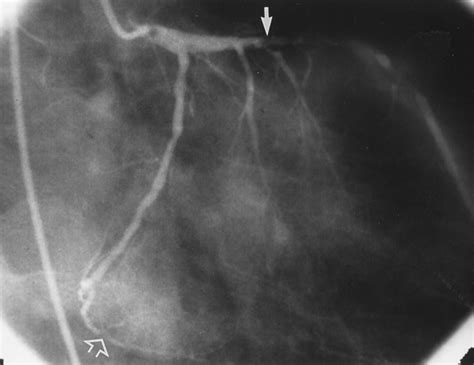

Transient Ischemic Dilation is defined as the apparent increase in the size of the left ventricular (LV) cavity on post-stress MPI images compared to rest images. This phenomenon is typically observed in patients undergoing either exercise or pharmacological stress testing. While the heart muscle does not actually change size in such a short window, the visual "stretching" or dilation effect is a surrogate marker for extensive, multi-vessel myocardial ischemia or severe left main coronary artery disease.

When the heart is subjected to stress, restricted blood flow in multiple coronary arteries leads to a widespread reduction in myocardial uptake of the radiotracer. This global subendocardial ischemia results in the apparent widening of the LV cavity when the stress images are compared to the rest images, where perfusion might appear more uniform. Recognizing Transient Ischemic Dilation is therefore a vital skill for cardiologists and radiologists, as it flags patients who are at a significantly higher risk for major adverse cardiac events.

1. Coronary Angiography: Invasive visualization of the coronary arteries to determine the exact degree of stenosis.